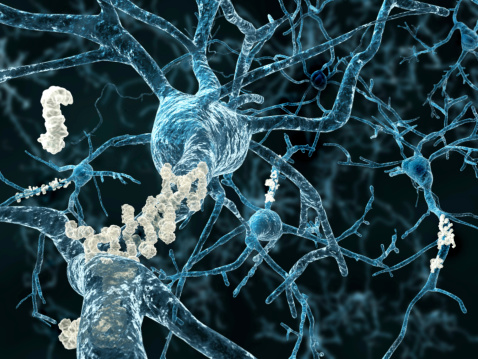

Over time, toxins can help the formation of plaques in your brain tissue that can trigger degenerative diseases like dementia and even Alzheimer’s disease, but home remedies can help combat these toxins and protect your memory. Exercise and healthy eating are the two main remedies for a healthy brain, and they’re within our control. The ...click here to read more